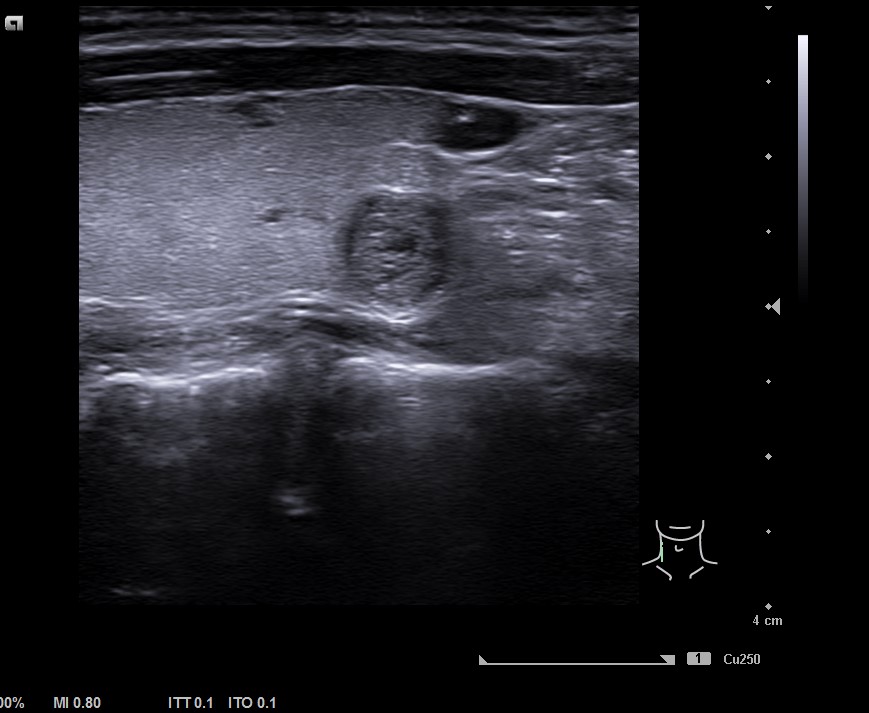

Lóbulo derecho de ecoestrucutra normal. Presenta nódulos hipoecogénicos, pero de características espongiformes y vascularización periférica en situación posteroinferior de 7,5 mm de diámetro, bien definido. TIRADS 2.